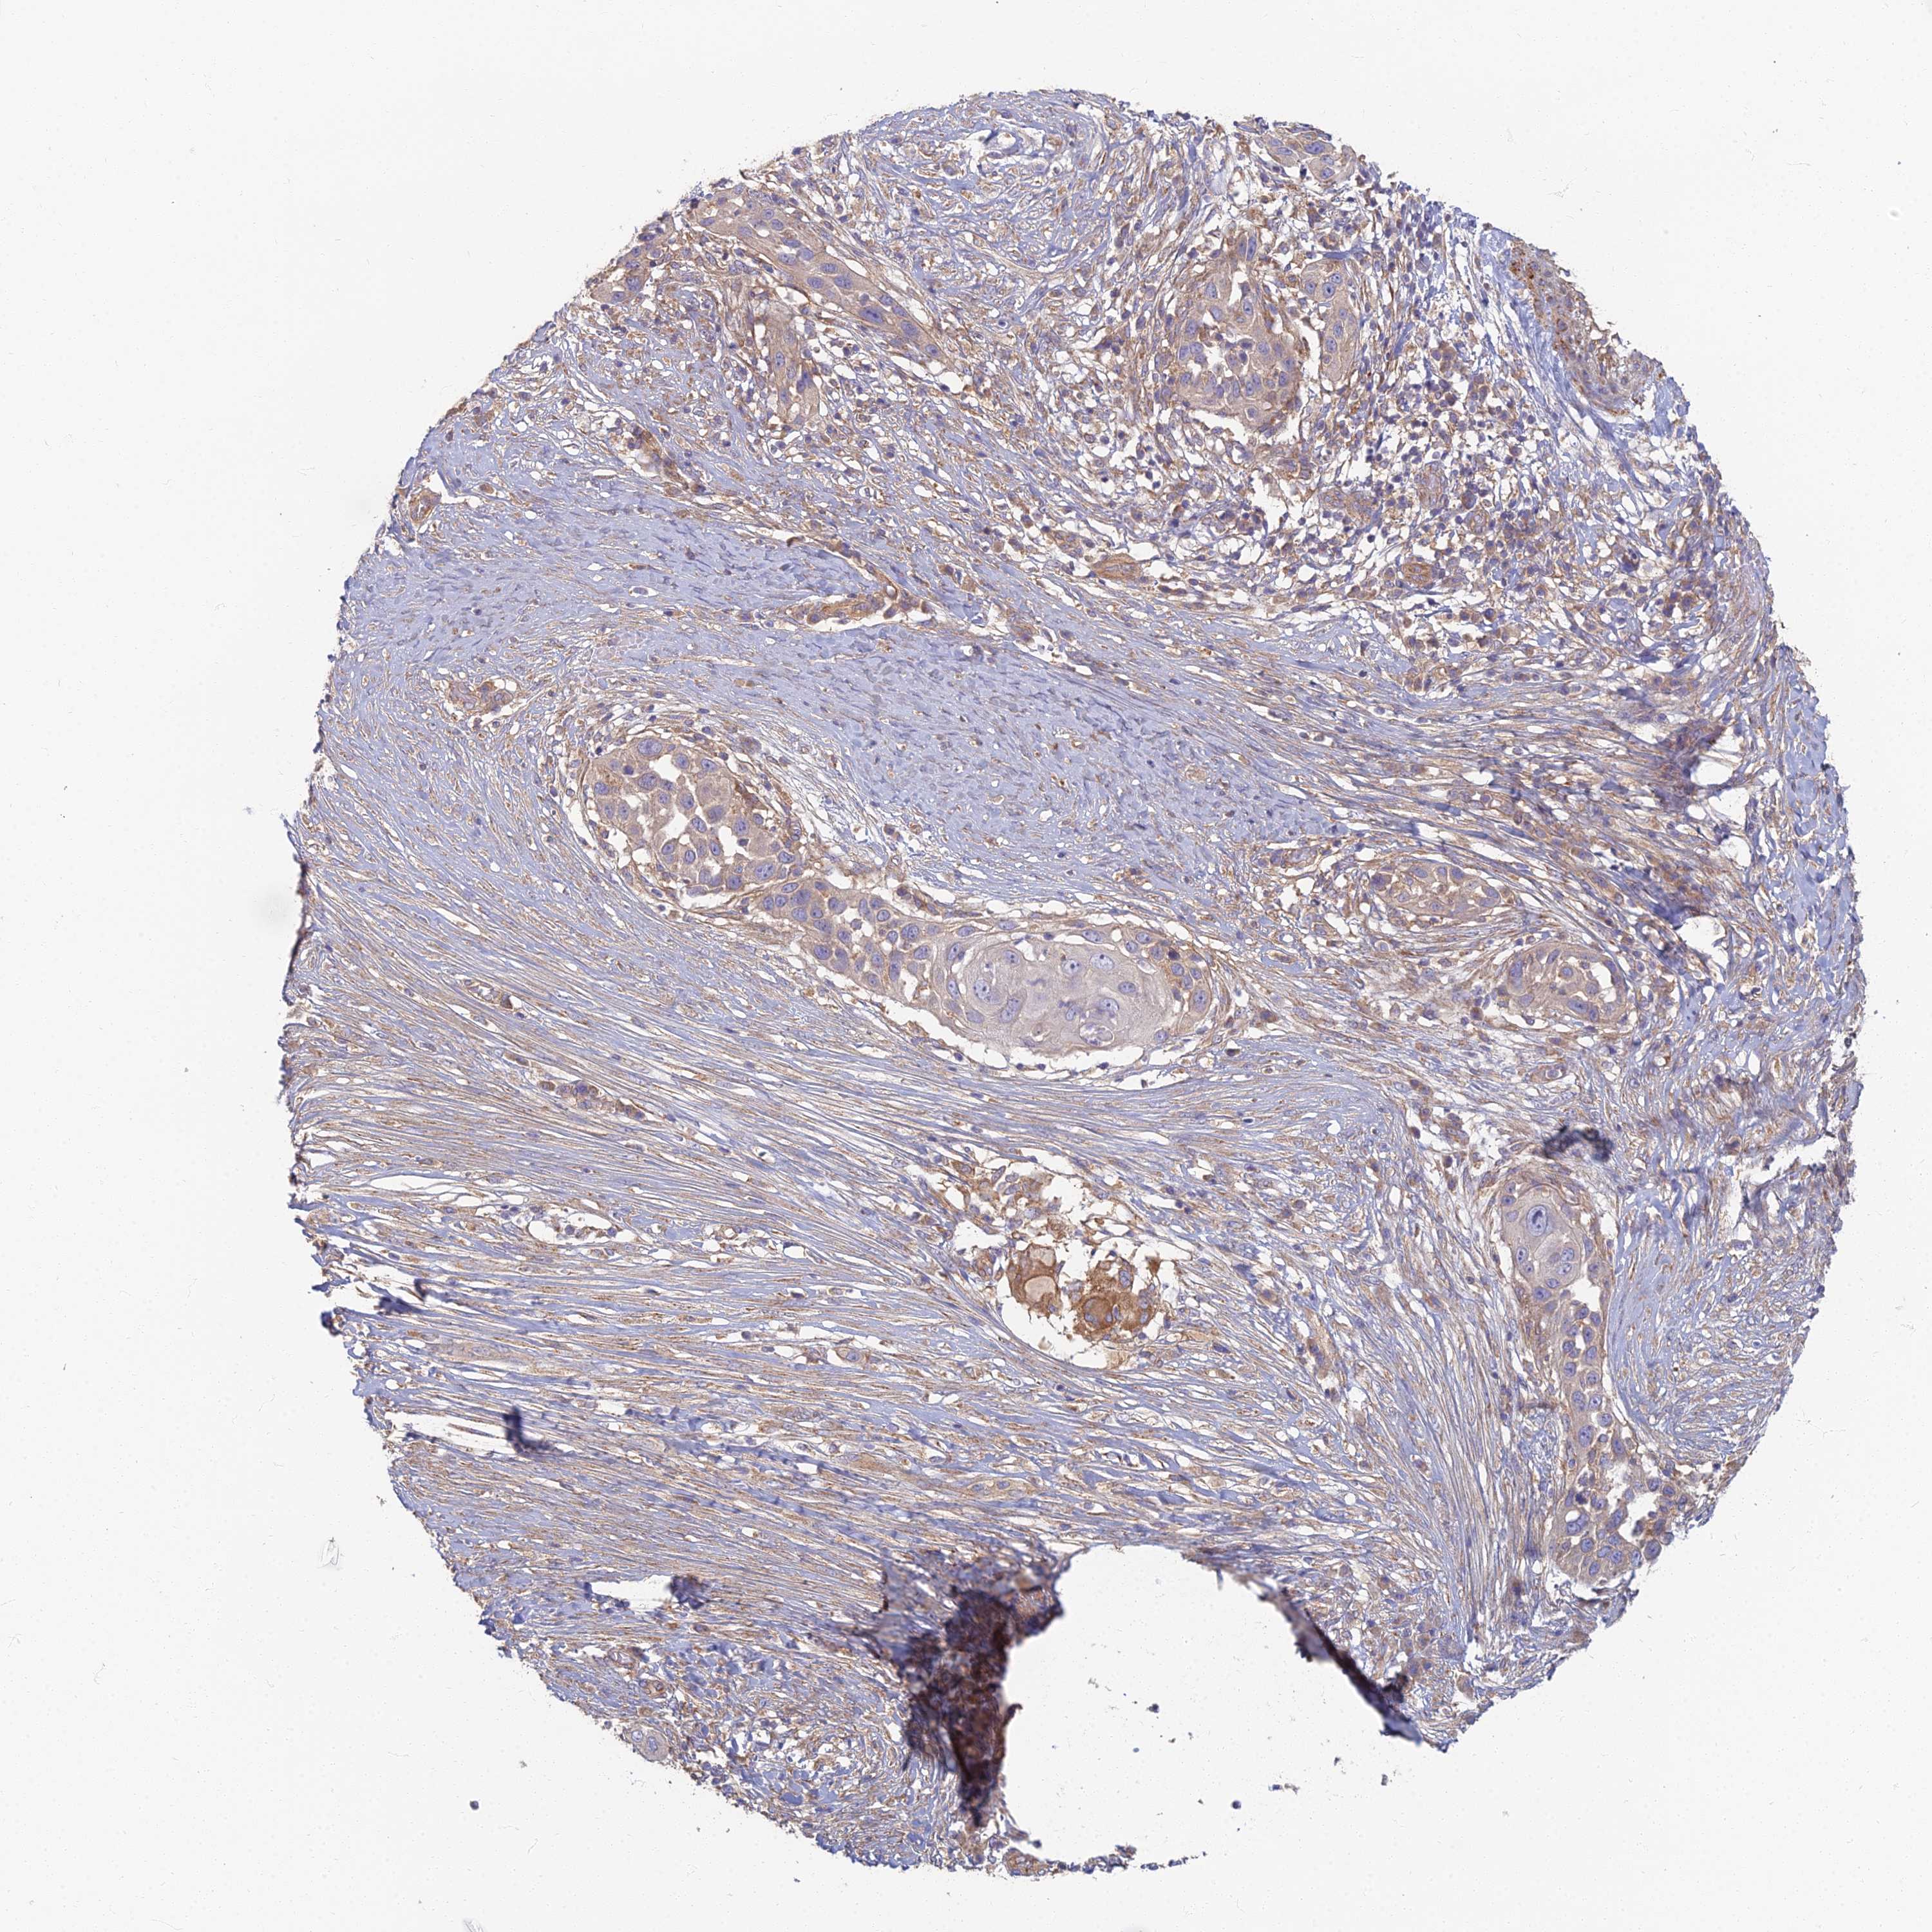

SKIN CANCER - Protein expressioni

A mouse-over function shows sample information and annotation data. Click on an image to view it in a full screen mode. Samples can be filtered based on level of antibody staining by selecting one or several of the following categories: high, medium, low and not detected. The assay and annotation is described here.

Antibody stainingi

Antibody staining in the annotated cell types in the current human tissue is reported as not detected, low, medium, or high, based on conventional immunohistochemistry profiling in selected tissues. This score is based on the combination of the staining intensity and fraction of stained cells.

Each image is clickable and will lead to virtual microscopy that enables deeper exploration of all samples and also displays staining intensity scores, fraction scores and subcellular localization as well as patient and tissue information for each sample.

Antibody HPA044878

Staining

High

Medium

Low

Not detected

Intensity

Strong

Moderate

Weak

Negative

Quantity

>75%

75%-25%

<25%

None

Location

Nuclear

Cytoplasmic/membranous

Cytoplasmic/membranous,nuclear

Squamous cell carcinoma, NOS